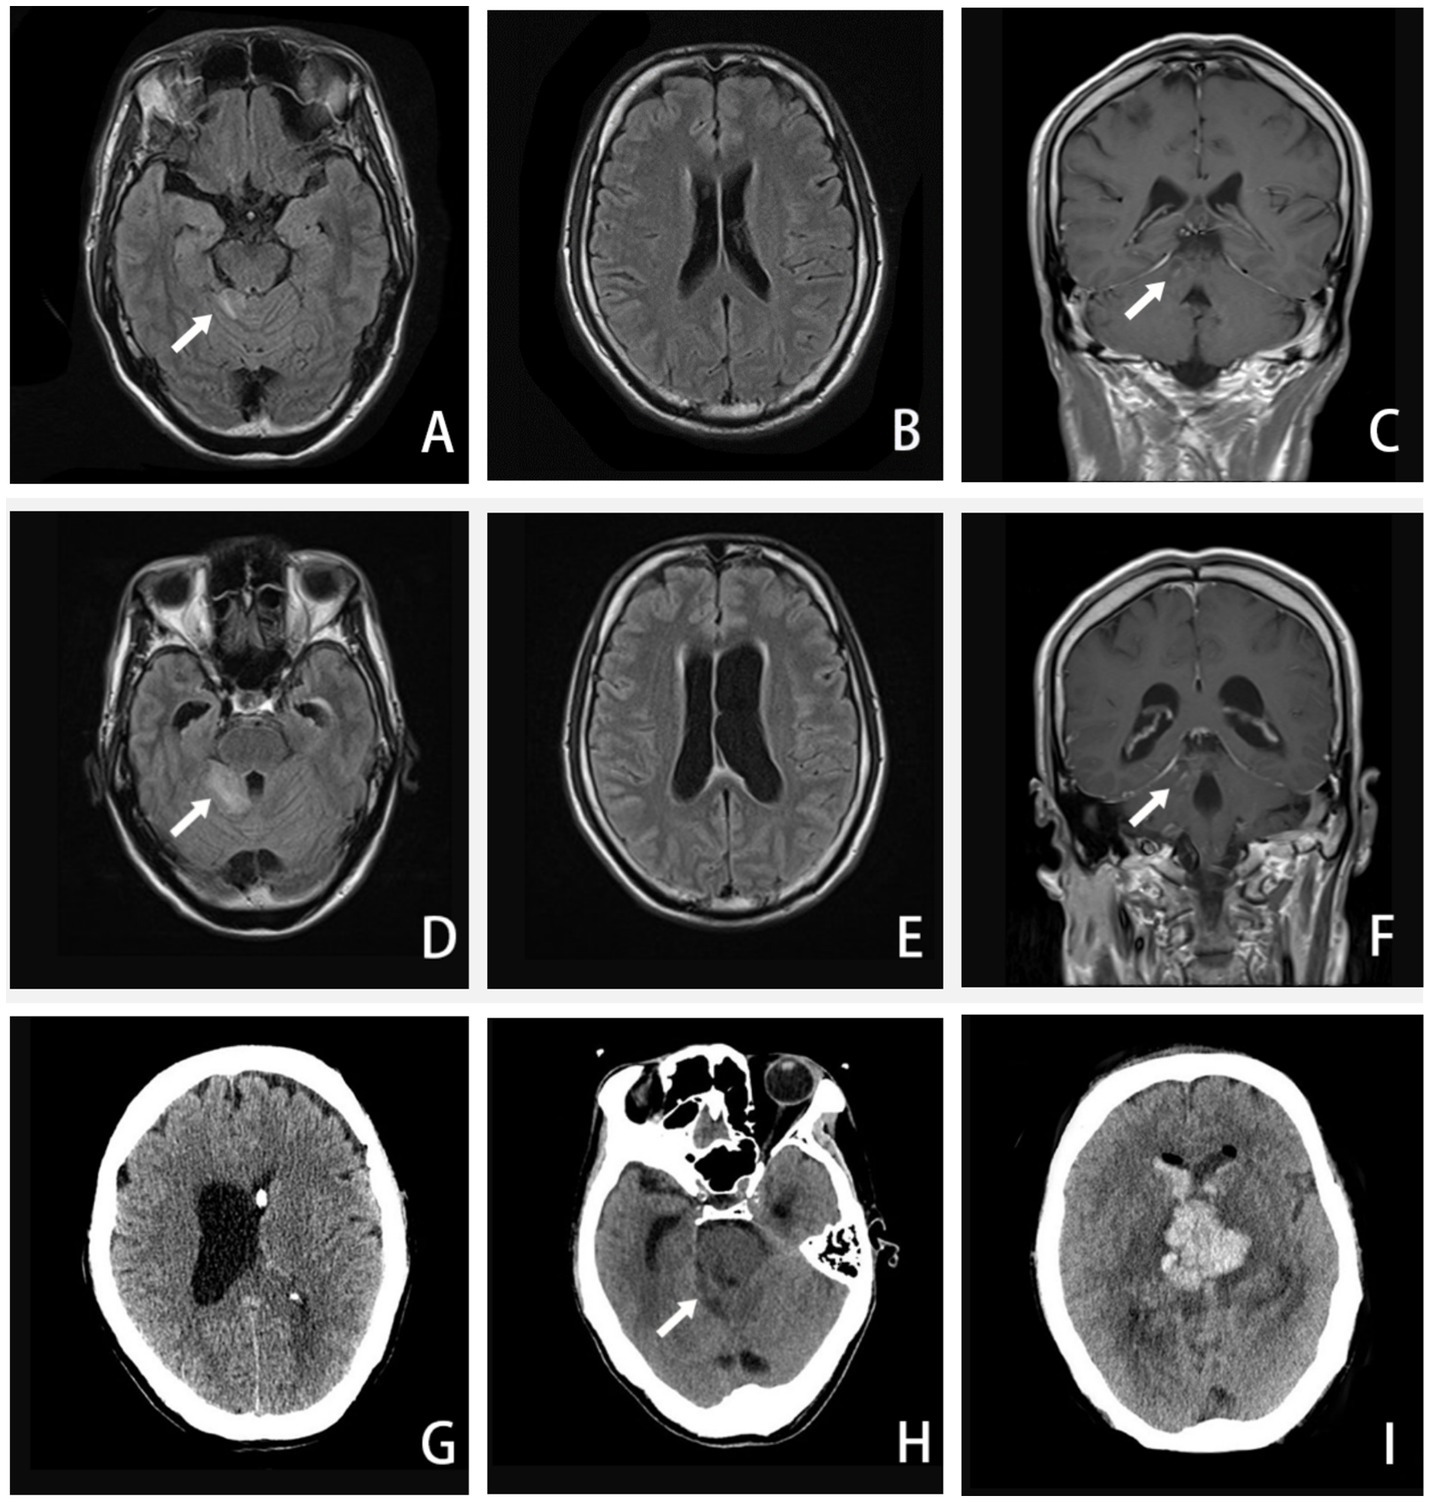

Figure 2

A–C, Axial FLAIR image and coronal T1-weighted enhanced image (16 September 2020) showing enhanced lesions on the cerebellar vermis and meninges. D–F, Axial FLAIR image and coronal T1-weighted enhanced image (24 September 2020) showing extended area on the cerebellar vermis lesion, along with ventricular expanded, especially the left side. G, CT image (27 September 2020) showing the left-side ventricular compressed by the expanded right-side. H–I, CT image (5 October 2020) showing the brainstem and ventricle with diffuse brain edema, inflammatory spread to the brainstem and the contralateral cerebellum, hemorrhage in the right-side of cerebellar vermis lesion. (The arrow in A, C, D, and F points to an enhanced lesion on the cerebellar vermis; the arrow in H points to brainstem and ventricle with brain edema).

Three days later, we were unexpectedly informed that the NGS result revealed an infection with an amoeba genus called Balamuthia mandrillaris (Figure 1). The second CSF test showed a higher CSF pressure and an increased leukocyte count compared to the first test, accompanied by a significant depletion of glucose. In addition, an enhanced brain MRI (Figures 2A–C) revealed extensive meningeal thickening and a lesion in the cerebellar vermis. Based on these findings, the patient was diagnosed with amoebic meningoencephalitis and treatment was initiated as follows: intravenous ceftriaxone 4 g/qd (one time a day), fluconazole 0.6 g/qd, and amphotericin B liposomes (started at an initial dose of 5 mg per day, gradually increasing to 40 mg per day). In addition, oral sulfamethoxazole 0.96 g/q8h (once every 8 h) and metronidazole 0.8 g/tid (three times a day) were prescribed. To alleviate intracranial inflammation and pressure, prednisone 20 mg/qd and mannitol 25 g/q12h (once every 12 h) were administered in combination.

Around the 14th day, the patient experienced a deterioration in consciousness and cognition, developing symptoms such as somnolence, memory dysfunction, disorientation in terms of time and place, nystagmus, worsening dizziness, and headache. A repeat MRI (Figures 2D–F) revealed an extended lesion in the cerebellar vermis and an enlargement of the left lateral ventricle, indicating obstructive hydrocephalus. With the consent of his family, our neurosurgeon performed a left-sided lateral external ventricular drain (LEVD) procedure on the patient. Following the surgery, he was transferred to the neurological intensive care unit (NICU) for further management.

Despite the interventions, the disease continued to progress. Three days after the initial left-sided LEVD, the patient required a right-sided LEVD, endoscopic third ventriculostomy (ETV), and intraventricular lavage due to obstruction of the drainage tube and worsening hydrocephalus evident on cranial CT (Figure 2G), which showed significant expansion of the right lateral ventricle. During the ETV procedure, a large amount of inflammatory exudate was observed covering the pia mater through the ventriculoscope (Figure 3). Histopathological examination of a small piece of brain tissue revealed inflammatory infiltration with neutrophils, but no trophozoites or cysts were present (Figure 4). These findings indicated an aggravating inflammatory response in the brain.

Twenty-four days after admission, the patient’s condition deteriorated significantly. In the morning, he experienced a seizure and rapidly progressed to a deep coma, accompanied by hypotension and loss of spontaneous breathing. His neurologic examination revealed mydriasis and the disappearance of brainstem reflexes. An urgent cranial CT examination showed a hemorrhage in the brainstem and ventricles, along with extensive brain edema (Figures 2H,I). Despite a week of life-sustaining therapy, the patient was eventually declared brain dead after evaluations using somatosensory evoked potential (SEP), electroencephalogram (EEG), and transcranial Doppler (TCD). Following this, his family decided to withdraw active treatment, and life support was withdrawn. The patient passed away 33 days after the onset of the disease (Table 1).